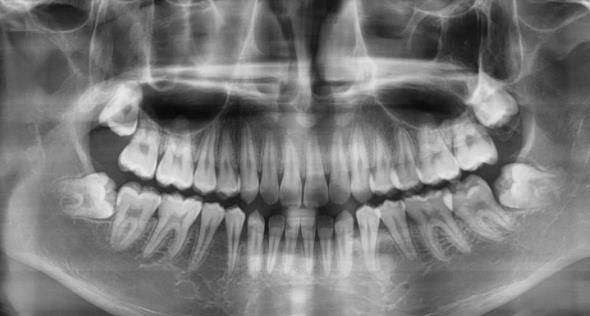

全景片,也叫曲麵斷層片

全景片,顧名思義(yi) 就是可以看到全部牙齒的牙片,這樣不僅(jin) 可能看到牙齒數量,確定是否缺失牙,而且還能看到牙槽骨是否有吸收的情況,有無多生牙、埋伏牙等。還有口內(nei) 是否有其他牙齒修複體(ti) 等等,看完後醫生對口內(nei) 牙齒情況一目了然。